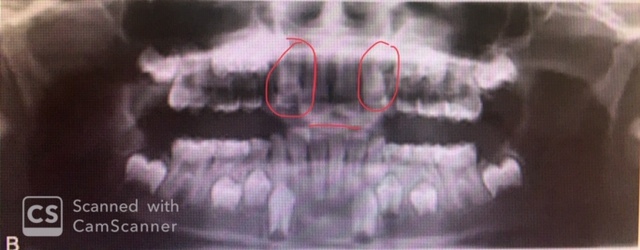

1.

Full metal crowns form bridge abutments

Identify the age of this patient

Age 12

Age 8

4

Identify the following:

PDL Space